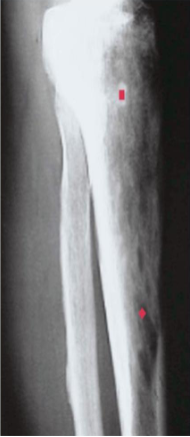

Osteopetrosis

AKA Marble bone disease, Albers-Schonberg disease

Impaired osteoclasts b/c impaired acidification of resorption pits → ↓ osteoclast bone resorption → diffuse symmetric skeletal sclerosis → stone-like bones/ abnormally radio-dense

↑ abnormal bone mass, brittle bones which break like chalk

Sclerotic/marble like thick, heavy but brittle bones → Fracture easily

Ends of bones are bulbous → Ehrlenmeyer flask deformity

Bones lack medullary canal (Primary spongiosa persists) → ↓ hematopoiesis → Leukopenia, anemia, thrombocytopenia (pancytopenia)

Extensive extramedullary hematopoiesis → hepatosplenomegaly

Small neural foramina → compression of nerves → blindness, deafness, facial paralysis

Roots of teeth are difficult to visualize

Dx: radiographs showing abnormally dense bones/diffuse symmetric sclerosis